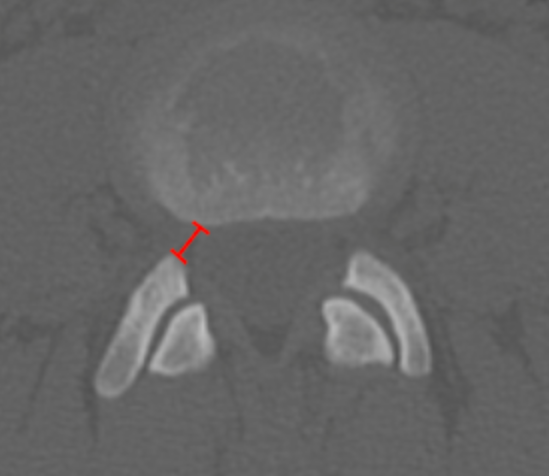

Lateral Recess Depth/Width